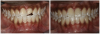

For the case in Figure 9 through Figure 11, the patent presented for an initial consultation with bonding completed on teeth Nos. 7 through 10 a few years prior with a chief complaint of not liking the way the resin bonding looked and how it was wearing. Up to this point, the bonding had repeatedly chipped and been repaired three times already. The patient's canines also exhibited signs of incised wear and flattening, which she did not like. Based on the patient's goals for her smile and her financial budget, she elected to have porcelain veneers completed on teeth Nos. 6 through 11. The total esthetics of the case design were somewhat limited given that the patient's esthetic zone included her posterior teeth and mandibular anterior teeth. Therefore, the color and characteristics of the veneers had to match her existing dentition closely.

In another case, the patient presented with very thick, bulky, over-contoured veneers done on teeth Nos. 7 through 10 when she was a teenager. There also was some recession and staining at the margins (Figure 12). The clinician decided to restore teeth Nos. 6 through 11. A preparation design was required with provisionals removed. As tooth structure could not be regrown, the practitioner made the best of the situation. There was good gum health, which is important for isolation and marginal seal. The clinician cemented with a universal, doing six units at one time. Minimal cleanup was required. At a 1-month follow-up visit, although tissue still was settling in, the contours were natural. After a year (Figure 13), the gum filled in nicely and was in excellent health, and there was good color stability and seamless marginal integrity.